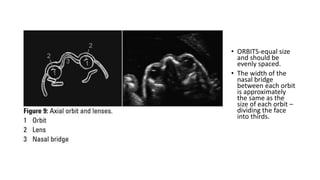

• ORBITS-equal size

• The width of the

nasal bridge

between each orbit

is approximately

the same as the

size of each orbit –

dividing the face

into thirds.

• ORBITS-equal size andshould be evenly spaced. • The width of the nasal bridge between each orbit is approximately the same as the size of each orbit – dividing the face into thirds.

• #18 The orbits should be equal size with the gap between each orbit approximately the same as the width of each orbit (dividing the face into thirds). The lenses can be seen as central circles that should not have internal echogenicity. Lens opacity may indicate congenital cataracts